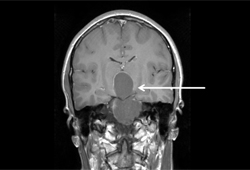

Neuroma acústico: ressonância nuclear magnética (RNM) coronal pós-contraste

Do acervo do Ryojo Akagami; usado com permissão